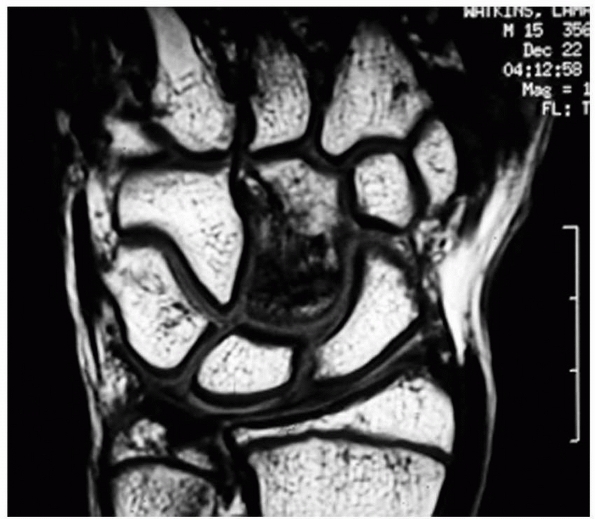

common findings that require further diagnostic evaluation. Aside from

standard laboratory testing, magnetic resonance imaging (MRI) is

important for diagnosis of an inflammatory synovitis or tenosynovitis.